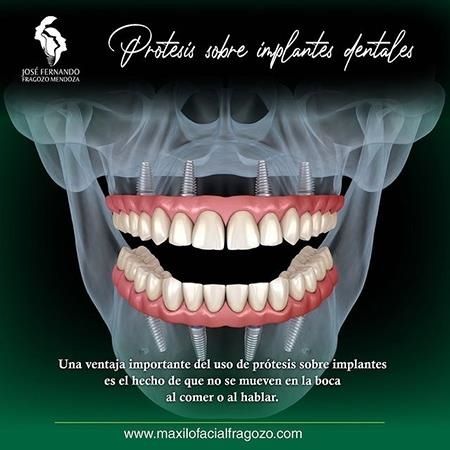

Procedimientos y tratamientos:

Me realice 2 implantes dentales. Un implante en la parte superior derecha y el otro implante en la parte inferior izquierda. El Dr. Fragozo fue muy paciente y profesional. La recuperación después de los implantes fue muy satisfactoria. El Dr. estuvo muy pendiente de mi. Hoy en día que tengo mis dos implantes no he tenido ningún tipo de dolor ni inconvenientes. Muy satisfecha con el trabajo del Dr. Lo recomiendo a un 100% para implantes dentales.